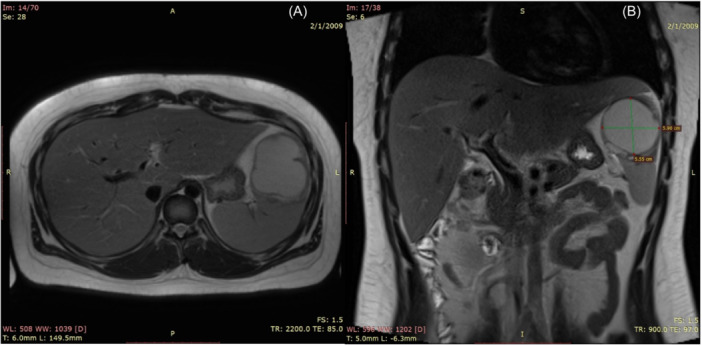

Salmonella splenic abscess.